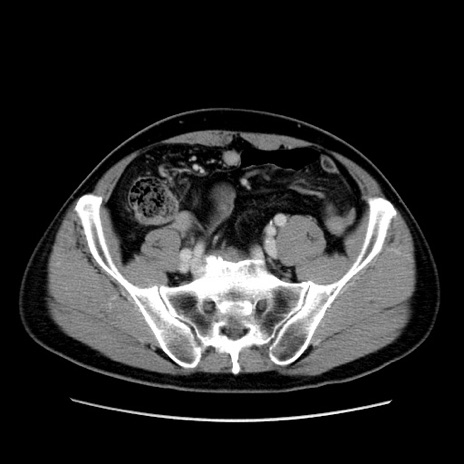

症例34(横断像)

【症例】60歳代 男性

【主訴】右鼠径部膨隆

【現病歴】1年程前より右鼠径部膨隆あり。自己にて還納可能だったため放置していた。3時間前より右鼠径部の脱出を認め、還納困難となり受診。

【既往歴】高血圧

【身体所見】右鼠径部に小児頭大の膨隆あり。弾性硬であり、用手還納は困難。左鼠径部にも膨隆を認める。脱出はなし。

【データ】WBC 15500、CRP 測定なし